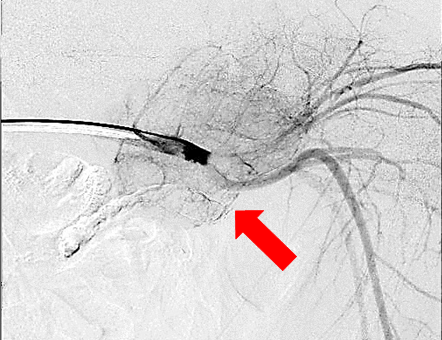

【実施症例】腋窩に発生したメラノーマに対する動注療法

ラブラドール・レトリーバー、雄、12歳。

腋窩に発生した腫瘍によって跛行を呈していた。腋窩動脈から分岐する腫瘍栄養血管に抗がん剤を注入。 実施後腫瘍の縮小が得られ跛行が改善した。

腋窩に発生した腫瘍

腫瘍栄養血管

抗がん剤の選択的注入

実施前

実施後